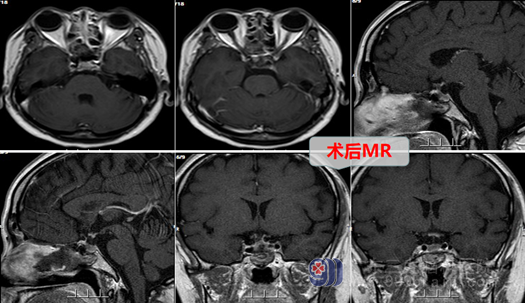

小银在七年前发现自己月经不规律,期间也有到医院寻医问诊,吃了药后也稍有好转,但就在一年前,小银觉得应该好得差不多了就自行停了药不吃了,可是,接下来左等右等月经就是不来了,这下小银可乱了神,自己结婚才刚过七年之痒,还没抱上小孩怎么就闭经了呢?就连忙到医院查了头颅MR发现是鞍区占位性病变,小银一时拿捏不好,在好朋友的介绍下,慕名来到了广东三九脑科医院找到了欧阳辉教授,欧阳教授耐心的接待了小银,查看了她的影像资料后解释道:“这是一种良性的病变,是一个囊肿,它压迫了正常垂体,经鼻微创手术即可解决问题,预后良好”,取得小银和其家属的同意后,欧阳辉教授团队在内镜下为小银进行了经鼻蝶鞍区Rathke’s囊肿开窗引流手术,手术进行得非常顺利,术后的小银也没有出现后遗症,激素水平逐渐恢复。我们也祝愿小银康复后能如愿怀上一个大胖小子。